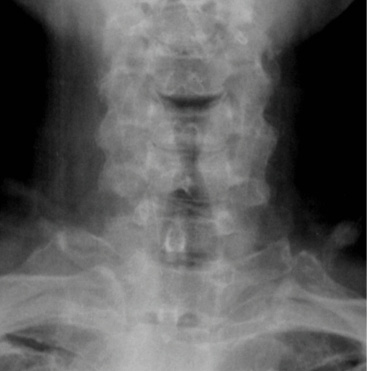

Pre-op dynamic radiographs demonstrate partial loss of disc height at C5-6 and C6-7 without instability or scoliosis.

The patient’s symptoms have completely resolved. The x-rays in Figure 8 were taken at the first post-op visit at 2 weeks.